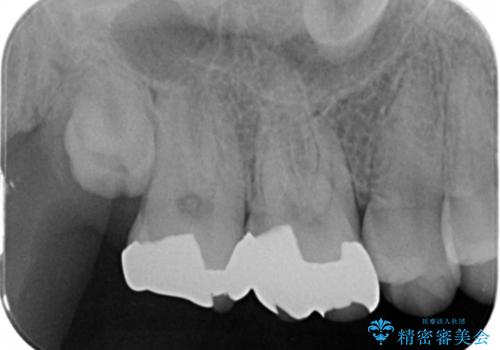

- 銀歯を白くしたいとのことで来院されました。

詰め物が覆っている面積が大きいため、強度を考慮してセラミックインレーではなくクラウンでの修復処置を進めていきます。

- 右上67 仮歯+ジルコニアクラウン:11,000円×2+121,000円×2 費用は治療当時の料金となります

奥歯で咬合力の負担を考慮した結果、インレーやアンレーではなくクラウンをおすすめする場合があります。